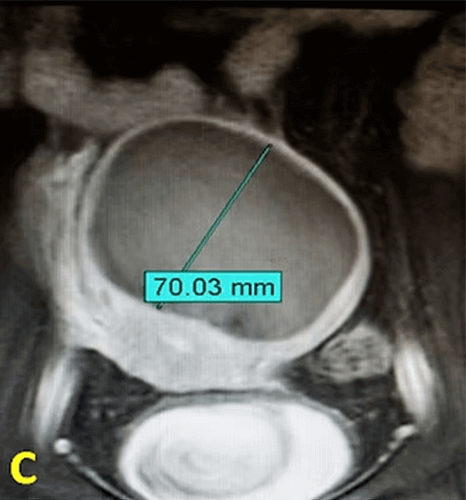

In our patient with a large uterine fibroid, embolization (UFE) was performed. After the procedure, the fibroid underwent complete necrosis and its diameter was reduced from 140mm to 70mm, while the normal uterine tissue remained viable.